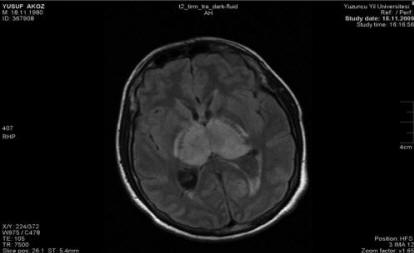

Magnetic Resonance Imaging Findings In Bilateral Basal ...

MRI Findings in Bilateral Basal Ganglia Lesions—Tchoyoson CC Lim Introduction The Basal Ganglia The deep grey matter structures of the basal ganglia comprise the caudate nucleus, putamen and globus pallidus. They form the key components of the extrapyramidal motor system, ... Document Retrieval

60 PLMS Following Stroke Figure 1. Axial and coronal diffusion-weighted imaging reveals acute infarction in the right globus pallidus and adjacent area. ... Return Document